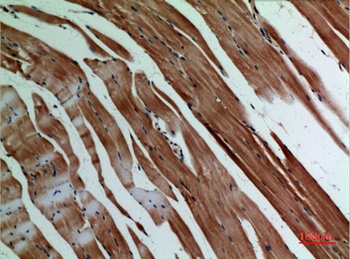

α-SMA Polyclonal Antibody

Catalog Number: orb1411650

| Catalog Number | orb1411650 |

|---|---|

| Category | Antibodies |

| Description | Rabbit polyclonal antibody to α-SMA. |

| Clonality | Polyclonal |

| Species/Host | Rabbit |

| Conjugation | Unconjugated |

| Reactivity | Human, Mouse, Rat |

| UniProt ID | P68133 |

| Tested applications | IHC-P, WB |

| Dilution range | WB: Western Blot: 1/500 - 1/2000. IHC-p: 1:100-300 ELISA: 1/20000. Not yet tested in other applications. |

| Storage | Maintain refrigerated at 2-8°C for up to 2 weeks. For long term storage store at -20°C in small aliquots to prevent freeze-thaw cycles |

| Alternative names | ACTA1; ACTA; Actin, alpha skeletal muscle; Alpha-a Read more... |

| Note | For research use only |